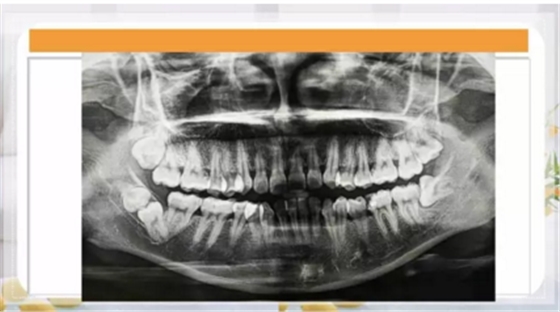

最近朋友圈轉(zhuǎn)發(fā)最多的一張片子,你知道嗎?

再看看逆襲的尖牙阻生。。。